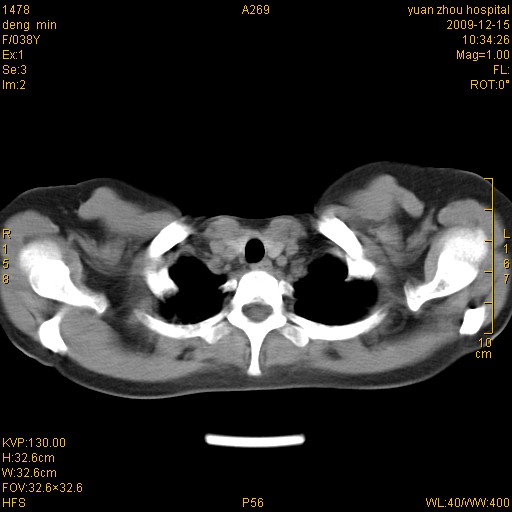

标题: CT23919:F38Y 咳嗽月余 [打印本页]

标题: CT23919:F38Y 咳嗽月余

右肺中下叶、左肺上叶舌段及左肺下叶支气管扩张合并感染。